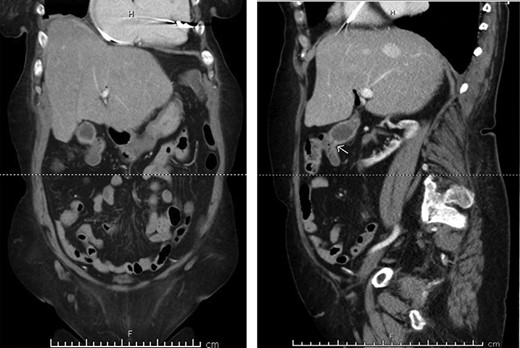

In this study, we were able to track the evolution of the patient’s cholecystoenteric fistulae. She was managed by the same surgeon over the 5 years from her initial episode of cholangitis to her eventual cholecystectomy. The initial CT scan taken during her hospitalization shows an inflamed gallbladder abutting the proximal transverse colon (Fig. 2). The CT enterography obtained 5 years later depicts a fistula that developed in this same region (coronal and sagittal views, Fig. 1). Intraoperatively, the fistula was also found at this location. It is difficult to ascertain when the fistula developed as the patient may have been asymptomatic for years.

CT scan of the same patient during her hospitalization for cholangitis 5 years prior; of note, there is close proximity between the gallbladder and proximal transverse colon; (a) coronal view (b) sagittal view.